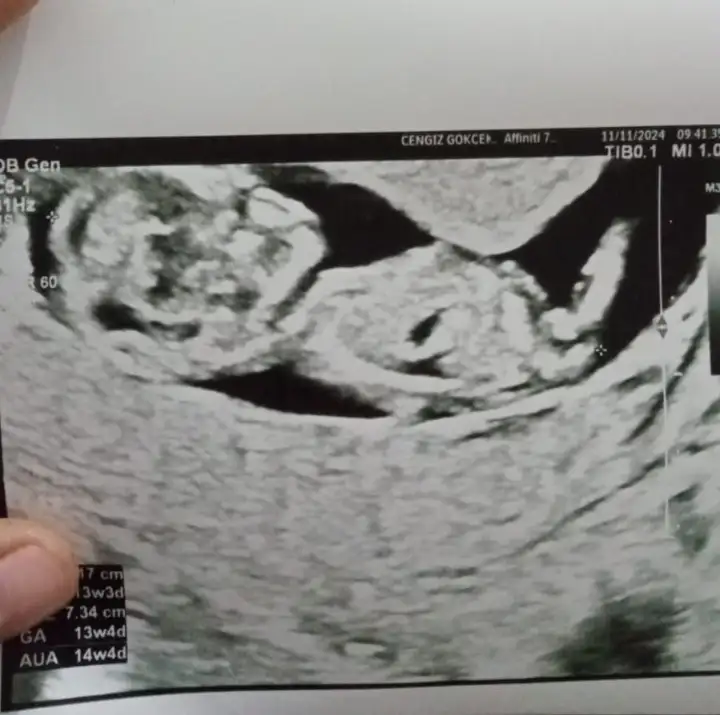

ErkekArkadaşlar 10 hafta 5 günlük hamileyim sizce cinsiyet ne olabilir

Banada bakabilirmisiniz 13 haftalıkBiraz hissiyat biraz görüntü

KizArkadaşlar 10 hafta 5 günlük hamileyim sizce cinsiyet ne olabilir

ErkekBanada bakabilirmisiniz 13 haftalık

Bana sizinki erkek gibi geldiİnşallah erkek olur sağlıcakla bir şekilde kucağınza alırsınız